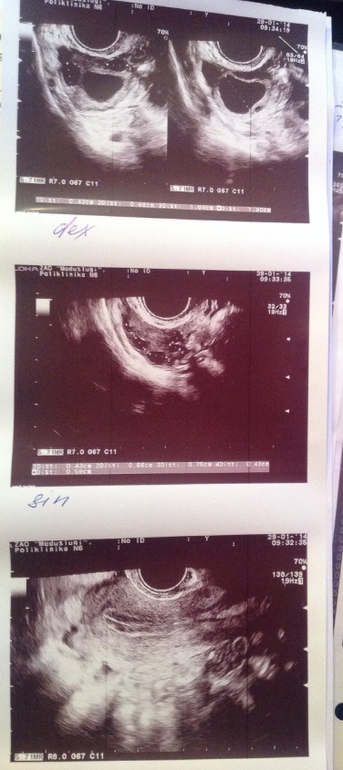

ФолликулометрияВсем привет.)Пишу первый раз, т.к. только начали планировать с мужем малыша.) Мечтала об этом давно, но возможность появилась только сейчас, поэтому желание забеременеть космических размеров!) Настал долгожданный месяц, мы старались от души. И сегодня , на 18 д.ц. ( овуляцияу меня на 15-18день) отправилась на узи посмотреть, все ли шло как хотелось. Узист мне выдал, что не видно желтого тела, и возможно овуляции не было. но при этом обнаружил жидость в позадиматочном пространстве, что вроде является признаком недавней овуляции. больше врач ничего не сказала... и мне показалось что она не совсем мастер своего дела. Девочки, подскажите пожалуйста, о чем говорят результаты, есть ли намек на овуляцию??Спасибо.

Большое спасибо, вы меня утешили!) Хотя узист напугал вдобавок, сказал что 25мл это большое кол-во жидкости. И она может быть результатом воспалительных процессов.